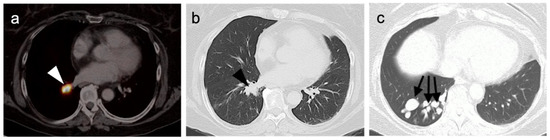

- Kayani, I.; Conry, B.G.; Groves, A.M.; Win, T.; Dickson, J.; Caplin, M.; Bomanji, J.B. A Comparison of 68Ga-DOTATATE and 18F-FDG PET/CT in Pulmonary Neuroendocrine Tumors. J. Nucl. Med. 2009, 50, 1927–1932. [Google Scholar] [CrossRef] [Green Version]

- Zidan, L.; Iravani, A.; Kong, G.; Akhurst, T.; Michael, M.; Hicks, R.J. Theranostic implications of molecular imaging phenotype of well-differentiated pulmonary carcinoid based on 68Ga-DOTATATE PET/CT and 18F-FDG PET/CT. Eur. J. Pediatr. 2020, 48, 204–216. [Google Scholar] [CrossRef]

- Tatci, E.; Ozmen, O.; Gokcek, A.; Biner, I.U.; Ozaydin, E.; Kaya, S.; Arslan, N. 18F-FDG PET/CT rarely provides additional information other than primary tumor detection in patients with pulmonary carcinoid tumors. Ann. Thorac. Med. 2014, 9, 227–231. [Google Scholar] [CrossRef]